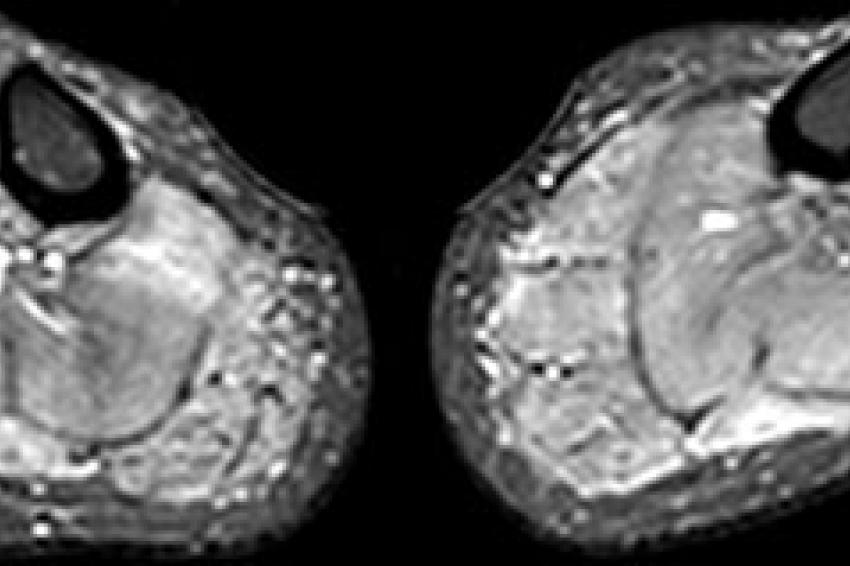

14-jähriges Mädchen mit florider Myositis der Oberschenkelmuskulatur, die sich in beidseits erhöhtem Signal der Muskeln (entsprechend ödematösen Veränderungen) und der Muskelfaszien auf den wassergewichteten, fettunterdrückten (STIR) MR-Aufnahmen zeigt (A).

Abzugrenzen von dieser schwerwiegenden Muskelentzündung sind reaktive Veränderungen nach sportlicher Betätigung, die sich auch mit ödematösen muskulären Veränderungen manifestieren können. Dies wird im Fall einer 31-jährigen gesunden Frau in den STIR-MR-Bildern demonstriert (B). Auch diese leichtgradigen ödematösen Veränderungen in der Unterschenkelbeugemuskulatur beidseits kann die MRT sehr sensitiv erfassen (B), die krankheitsspezifische Einordnung ist anhand rein morphologischer Kriterien oft schwierig.

Vergleichen Sie die Unterschenkel in (B) mit deutlichen ödematösen Veränderungen in der Unterschenkelmuskulatur bds. auf den STIR-Bildern bei einer 37-jährigen Frau mit Hypokaliämischer Periodischer Paralyse Typ-1 (C), bei der pathophysiologisch eine Wassereinlagerung und eine exzessive Na+-Akkumulation in den Muskelzellen vorliegt.